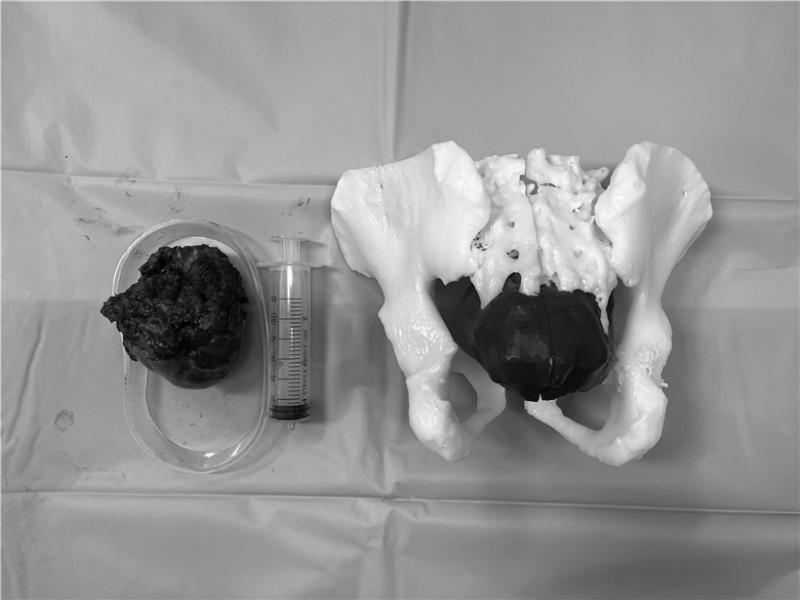

病灶巨大,达12厘米×9厘米,不仅破坏了骶骨骨质,还侵犯了臀大肌。此外,解剖位置较深,周围结构复杂,瘤体血运丰富,手术暴露困难,给切除带来了极大挑战。常黎明院长、廖光军主任团队多次在科内组织病例讨论,制定各种详尽的手术方式,包括肠道切除+直肠造瘘、皮瓣移植术等多个手术备选方案。同时运用3D打印技术,根据术前患者影像学数据,以1:1的比例3D打印骶骨模型,帮助术者更为清晰地了解和掌握肿瘤界限及侵犯程度,可以进行术前的规划和手术方案的优化,同时为患者及家属和术者提供触觉与视觉上的体验,帮助术者与患者及家属更有效地完成术前沟通。

术前,介入科帮助栓塞肿瘤滋养血管及安置腹主动脉球囊。在麻醉科、输血科保驾护航下,常黎明院长、廖光军主任团队术中利用3D打印模型,清晰明确了恶性肿瘤侵犯的软组织范围,骨破坏程度,需截骨的位置等,减少了术中X线透视的使用次数,简化了手术步骤,使术中出血量减少,复杂的骨肿瘤手术变得相对容易,最后历时3小时,出血2000毫升,顺利完成了手术。术后,王先生左侧骶3及以上神经得以保留,大小便功能未受损,刀口愈合良好。王先生对手术效果非常满意,现已顺利康复出院。